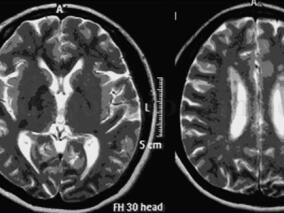

1小时条评论19岁男性,反复发作头痛伴抽搐,病程4年。病程初期反复发作头痛,无影像学改变。2年后头痛再次发作伴右侧偏盲,伴癫痫大发作,头颅MRI发现病灶,有枕叶癫痫反复发作;病后3年每隔10天发热头痛。病后4年头痛频繁,再次癫痫发作。该患者的诊断可谓一波三折。在该院最终...

1小时条评论线粒体脑肌病是由各种原因使线粒体DNA(mtDNA)和(或)核DNA(nDNA)发生基因突变,细胞内线粒体的结构与功能异常,导致细胞呼吸链及能量代谢障碍的一组疾病。由于对本病缺乏认识或因检查方法受限,常易误诊。下面这例病例,看专家如何慧眼识别该疾病。 临床资料 ...